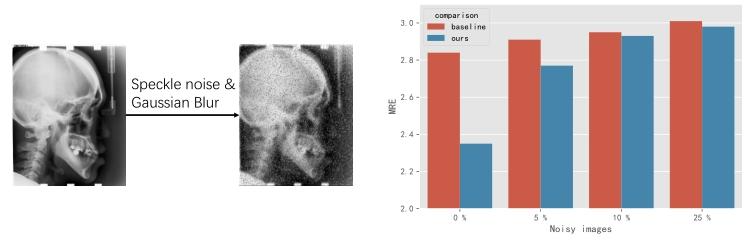

Fig. 7. (left) Add noise to images. (right) Results of noisy datasets.

图7 噪声实验结果 (左图)向图像中添加噪声的示意图